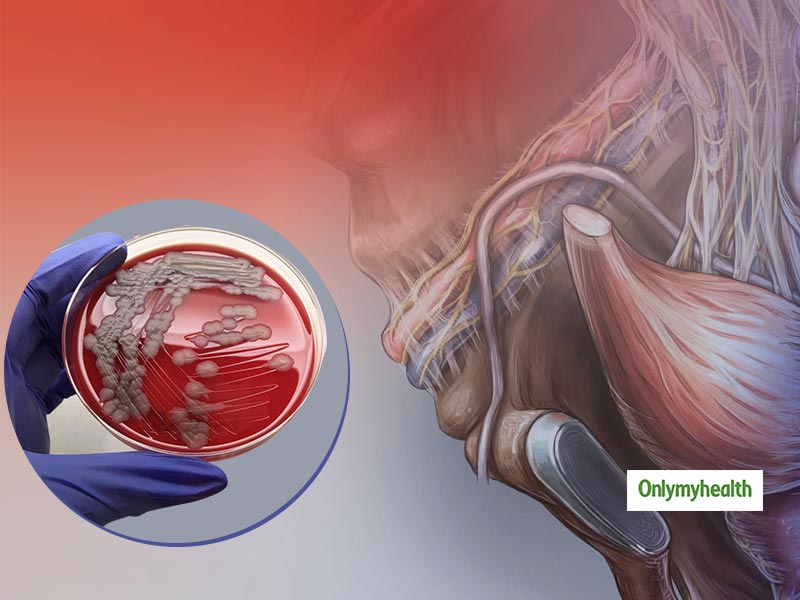

Anthrax is a notifiable animal disease.

How to cure anthrax. Inhalation anthrax can also be treated with a combination of antibiotics and injections of raxibacumab or obiltoxaximab (monoclonal antibodies that bind anthrax toxins in the. [4] anthrax vaccination is recommended for people at high risk of infection. Inhalational anthrax results from breathing anthrax spores into the lungs.

Doctors have several options for treating patients with anthrax, including antibiotics and antitoxin. While naturally occurring, it remains. [3] immunizing animals against anthrax is recommended in areas where previous infections have.

Introduction anthrax is an ancient zoonotic disease which primarily infects herbivores with humans occasionally being infected. Cutaneous anthrax is easy to cure if it is treated early with appropriate antibiotics. It is excellent for use in case.

How is anthrax in humans treated? If a domestic animal is sick or has just died, can its meat and. Patients with serious cases of anthrax need to be hospitalized.